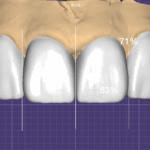

사진 2 – 무삭제 라미네이트를 살짝 올려놓은 상태

삭제 없이 제작한 라미네이트를 치아 위에 임시로 올려본 모습입니다.

치아를 전혀 손상시키지 않은 상태에서도 형태가 자연스럽게 개선되는 것을 확인할 수 있습니다.

이 단계에서 중요한 것은:

- 치아가 과도하게 커 보이지 않는지

- 입술과 얼굴 비율에 어울리는지

- 치아 끝의 투명감이 유지되는지

입니다.